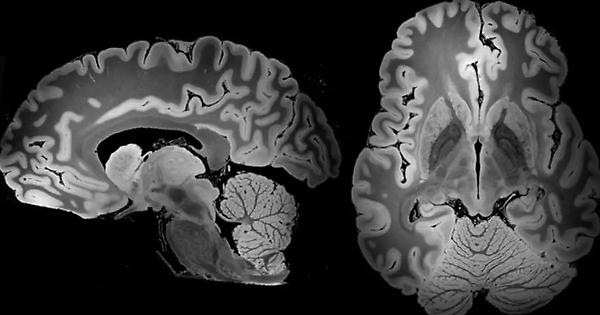

Quando si pensa all’applicazione delle neuroscienze nell’ambito della giustizia penale, la prima immagine che viene in mente è uno scan del cervello di un imputato a processo per omicidio a sostegno della sua infermità mentale. Questa immagine riflette perfettamente le note, tutt’ora dominanti, del dibattito internazionale sui possibili contributi delle neuroscienze al diritto. Dalla prova del vizio di mente alla c. d. “neuropredizione” della recidiva, le discussioni giuridiche sull’apporto delle neuroscienze in ambito penale continuano a ruotare intorno al ridondante “ bad or mad dilemma” ( traducibile con: i “ criminali” sono ‘ folli’ che vanno curati o ‘ cattivi’ che vanno puniti?”).

Negli ultimi dieci anni, questa domanda ha fatto da sfondo al mio lavoro di ricerca e di insegnamento universitario a cavallo tra Europa e Stati Uniti. In questo lavoro, sfociato in una serie di pubblicazioni giuridiche tra cui la mia recente monografia “ The Emotional Brain and the Guilty Mind: Novel Paradigms of Culpability and Punishment” ( Hart Publishing, 2021), ho sviluppato una contronarrativa di come le neuroscienze, in particolare le neuroscienze sociali, possano assurgere a strumento di umanizzazione della giustizia, dando sostegno all’affermazione di ideologie e pratiche che siano effettivamente in linea con proclamate esigenze di umanità, dignità e uguaglianza nel trattamento delle persone condannate. Attraverso l’analisi di studi sul bisogno neurobiologico universale di appartenenza sociale, sul fenomeno della c. d. neuroplasticità che sta alla base del cambiamento comportamentale, o sui danni cerebrali causati dall’isolamento e da ambienti degradanti, il mio lavoro mira a usare questo corpo di conoscenze scientifiche per contrastare logiche e pratiche istituzionali tendenti all’esclusione e alla dura punizione. Al contrario, supporta l’adozione di un modello di giustizia ancorato al valore della inclusione sociale e che si articoli in risposte sanzionatorie che offrano alle persone condannate concrete opportunità di cambiamento in positivo attraverso il contatto con luoghi sani e l’instaurazione ( o il mantenimento) di rapporti sociali stabili, inclusi i legami personali, il coinvolgimento in iniziative sociali, la partecipazione civica, l’istruzione universitaria e il lavoro adeguatamente retribuito.

Come spiego nei miei scritti, questo corpo scientifico offre un importante supporto empirico all’adeguatezza di approcci e risposte di carattere relazionale e reintegrativo ( tra cui, ma non solo, la giustizia riparativa) a promuovere il comportamento prosociale, e sta fornendo prova essenziale dei deleteri effetti neurobiologici che ambienti carcerari disumani, degradanti, e isolanti possono causare nelle persone ristrette — soprattutto tra quante abbiano pregressi traumatici— provocando, o aggravando, problemi di carattere psicologico e psichiatrico, e compromettendo il funzionamento sociale nel lungo periodo.

Gli studi di neuroscienze sociali gettano così ulteriore luce sulla necessità che i luoghi di giustizia ( soprattutto quelli detentivi) siano ambienti umanizzanti che favoriscano contatti sociali sani e stimolanti e dove le persone possano vivere la propria condanna in condizioni sicure, dignitose e, per quanto possibile, vicine alla vita reale. Detto altrimenti, i luoghi di giustizia non devono consistere in luoghi ove occultare esseri umani e problemi sociali, per dirla con Angela Davis, ma costituire opportunità di crescita, di responsabilizzazione, di superamento di traumi e di percorso al miglioramento attraverso il riconoscimento dei bisogni affettivi e sociali della persona e attribuendo a quest’ultima un ruolo attivo nel suo processo di cambiamento. Certamente, la scienza da sola non basta a supportare un tale cambiamento sistemico. Occorre una previa affermazione, o un rafforzamento, dei valori giuridici e sociali che animano gli scopi della giustizia, valori che certamente non devono rinunciare ad esigenze di certezza, proporzionalità ed equità nella risposta al reato, ma che riconoscano l’umanità universale delle persone condannate per favorire il pieno raggiungimento del nobile fine della ( re) integrazione sociale. Quindi no: la vera rivoluzione delle neuroscienze in ambito penale non sta nel fornire prove inedite dell’innocenza di un imputato. Più concretamente, per quanto complesso, il vero apporto offerto da questa branca del sapere sta nel contribuire ad umanizzare lo sguardo della giustizia penale verso le persone che ne sono implicate, sollecitando in tal modo una critica presa di coscienza degli scopi e della realtà dei suoi meccanismi sanzionatori alla luce delle evidenze empiriche.